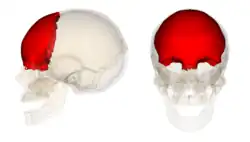

Frontal em destaque no crânio. Vista em 360°.

Frontal em destaque no crânio. Vista em 360°. -